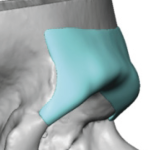

People considering custom jawline implants tend to ask a consistent set of questions. These generally fall into four categories: outcomes, safety, process, and recovery. What are custom jawline implants? Custom jawline implants are patient-specific implants designed from a 3D CT scan of your face. Unlike standard implants, they are digitally created to match your exact Read More…